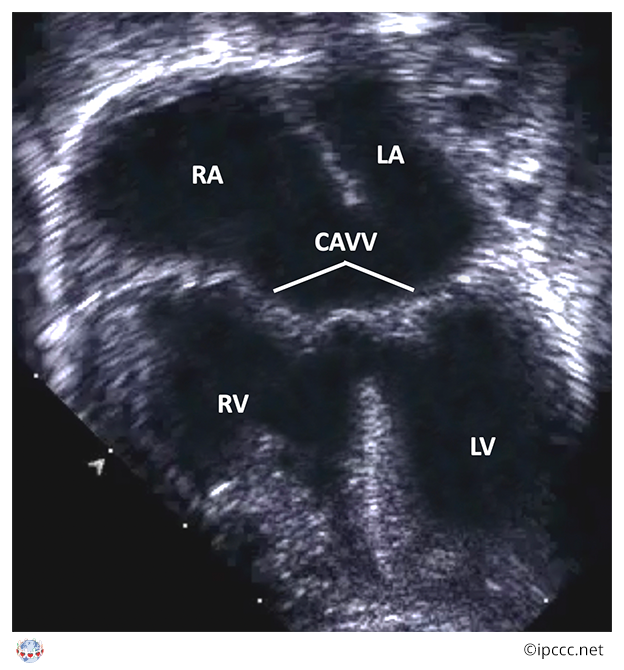

A congenital cardiac malformation that is a variant of an atrioventricular septal defect (atrioventricular canal defect) with an interatrial communication just above the atrioventricular valve, an interventricular communication just below the atrioventricular valve, and varying degrees of malformation of the left ventricular component of the common atrioventricular valve. There is unrestrictive interventricular communication (no interventricular pressure gradient) and the bridging leaflets usually float to varying extent within the atrioventricular septal defect.

Echocardiogram